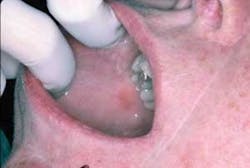

Dispersion throughout the mouth is also found in lichenoid reactions from the use of medications such as non-steoidal anti-inflammatory drugs and anti-high blood pressure medications. Figures 2 and 3 are from a patient who was taking Naprosyn. After discontinuing the medication, the tissue in Figure 3 was noticeably less inflamed. The patient took Tylenol during the two-week period and was later prescribed a different NSAID.